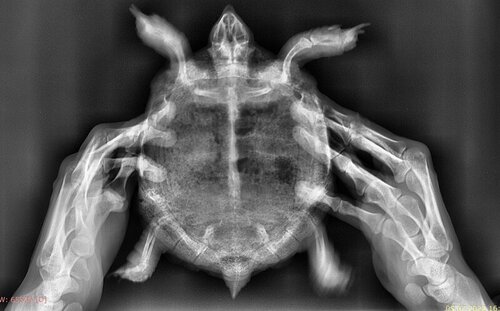

Панцырь очень сухой и на пластроне отслаивается

Вот, хотела показать,  сходили мы в больницу.

А то что внизу от руки написано, это тоже врач для пластрона написал: смазывать его раствором лимонной кислоты...

Черепаха да, авитаминозница (а не почки), но не в тяжёлой формы, лето на разнотравье и всё было бы ок. Получила бедняга такой передоз, что им опасно очень. Панцирь у неё не очень сухой, кстати, вполне обычно выглядит, ну кроме белесых растянутых полос роста... Кстати, это УФ+кальций, а не мел, нужен. То, что расслойки на пластроне, вполне обычное дело у бывших напольников, у вашей это ещё мизер, у моего самца до "залысин" отслойки. Сейчас главное, вообщем, чтобы "лечение" прошло без последствий, в остальном нет у чепы явных проблем.